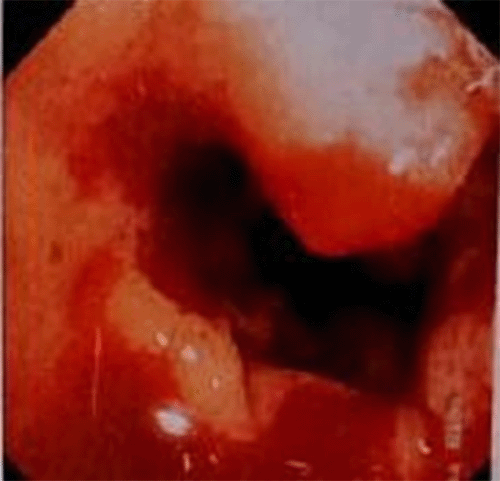

Figure 2. Colonoscopy Showing Nodular Area in Descending Colon. Published with Permission

A 42-year-old man presented with complaints of left-sided abdominal pain associated with bleeding per rectum of 30 days duration. He underwent a laparotomy for resection of a retroperitoneal malignant tumor in 2009; on histopathological examination, the tumor was consistent with malignant fibrous histiocytoma. The physical and rectal examination did not reveal any abnormalities. Complete blood count, serum electrolytes, creatinine, and urea were within the normal range, and screening for viral markers was negative. He underwent abdominal ultrasonography, which revealed a large rounded lesion, predominantly hypoechoic lesion of size more than 7.2 × 7.7 cm in the left hemipelvis, anterior to left iliac vessels and close to the midline. The lesion showed increased vascularity, and the site of the origin of the lesion could not be defined. Colonoscopy showed a nodular area with evidence of luminal compression and a visible vessel with an intermittent spur. Therapeutic intervention was not performed as there was no active bleeding.